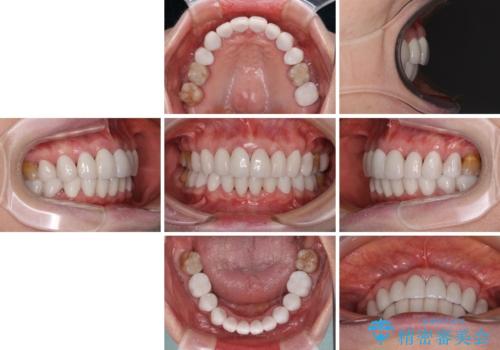

出っ歯を改善した後に真っ白な歯に 矯正歯科治療と審美歯科治療

- 口元の突出感と歯の色を気にして来院された患者様です。

口元を引っ込めるために上下左右第一小臼歯4本を抜歯し、ワイヤー矯正を行うこととしました。

歯の色はホワイトニングかセラミッククラウンで対応することとしましたが、ブラックトライアングルが目立つことが予想されたため、目立つ範囲をオールセラミッククラウンで補綴することとしました。

矯正治療をせず、セラミッククラウンので口元の突出感を改善しようとしても、神経を取り除く必要があったり、口元の突出感はあまり改善されなかったりと、後悔する可能性が高くなります。